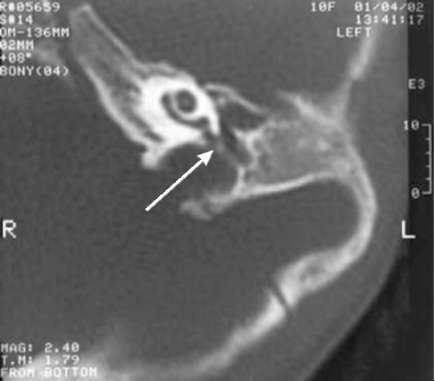

pic 0138

Рис.11-4. КТ, аксиальная проекция. Зона атрезии представлена преимущественно склерозированной костной тканью с единичными воздушными ячейками (КС). Небольшая, пневматизированная барабанная полость расположена на глубине 12 мм. Головка молоточка гипоплазирована, тело наковальни деформировано (ДС).

Рис.11-7. КТ, аксиальная проекция. Барабанная полость резко уменьшена в размерах, непневматизирована. Цепь слуховых косточек отсутствует. Структуры внутреннего уха и внутренний слуховой проход не изменены. Выявлено предлежание сигмовидного синуса (указано стрелкой).

Подробные данные КТ височной кости при оценке структур наружного, среднего и внутреннего уха у детей с врождёнными атрезиями наружного слухового прохода необходимы для оценки технической возможности формирования наружного слухового прохода, перспективности улучшения слуха, оценки степени риска предстоящей операции. Ниже приведены некоторые типичные аномалии (рис. 11-4-11-8).